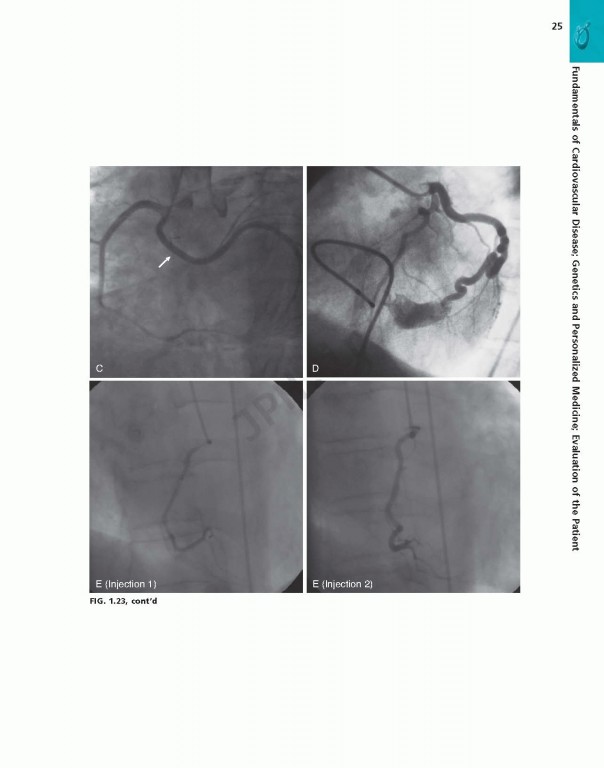

کتاب Braunwalds Heart Disease Review and Assessment 2019، بررسی و ارزیابی بیماری قلبی براونوالد ویراست یازدهم شامل تصاویر و تصاویر کاملاً رنگی که مطالعه شما را بهبود بخشیده و حفظ مواد پیچیده را بهبود می‌بخشد.

• Contains full-color images and illustrations throughout, and numerous case studies that enhance your study and improve retention of complex material.